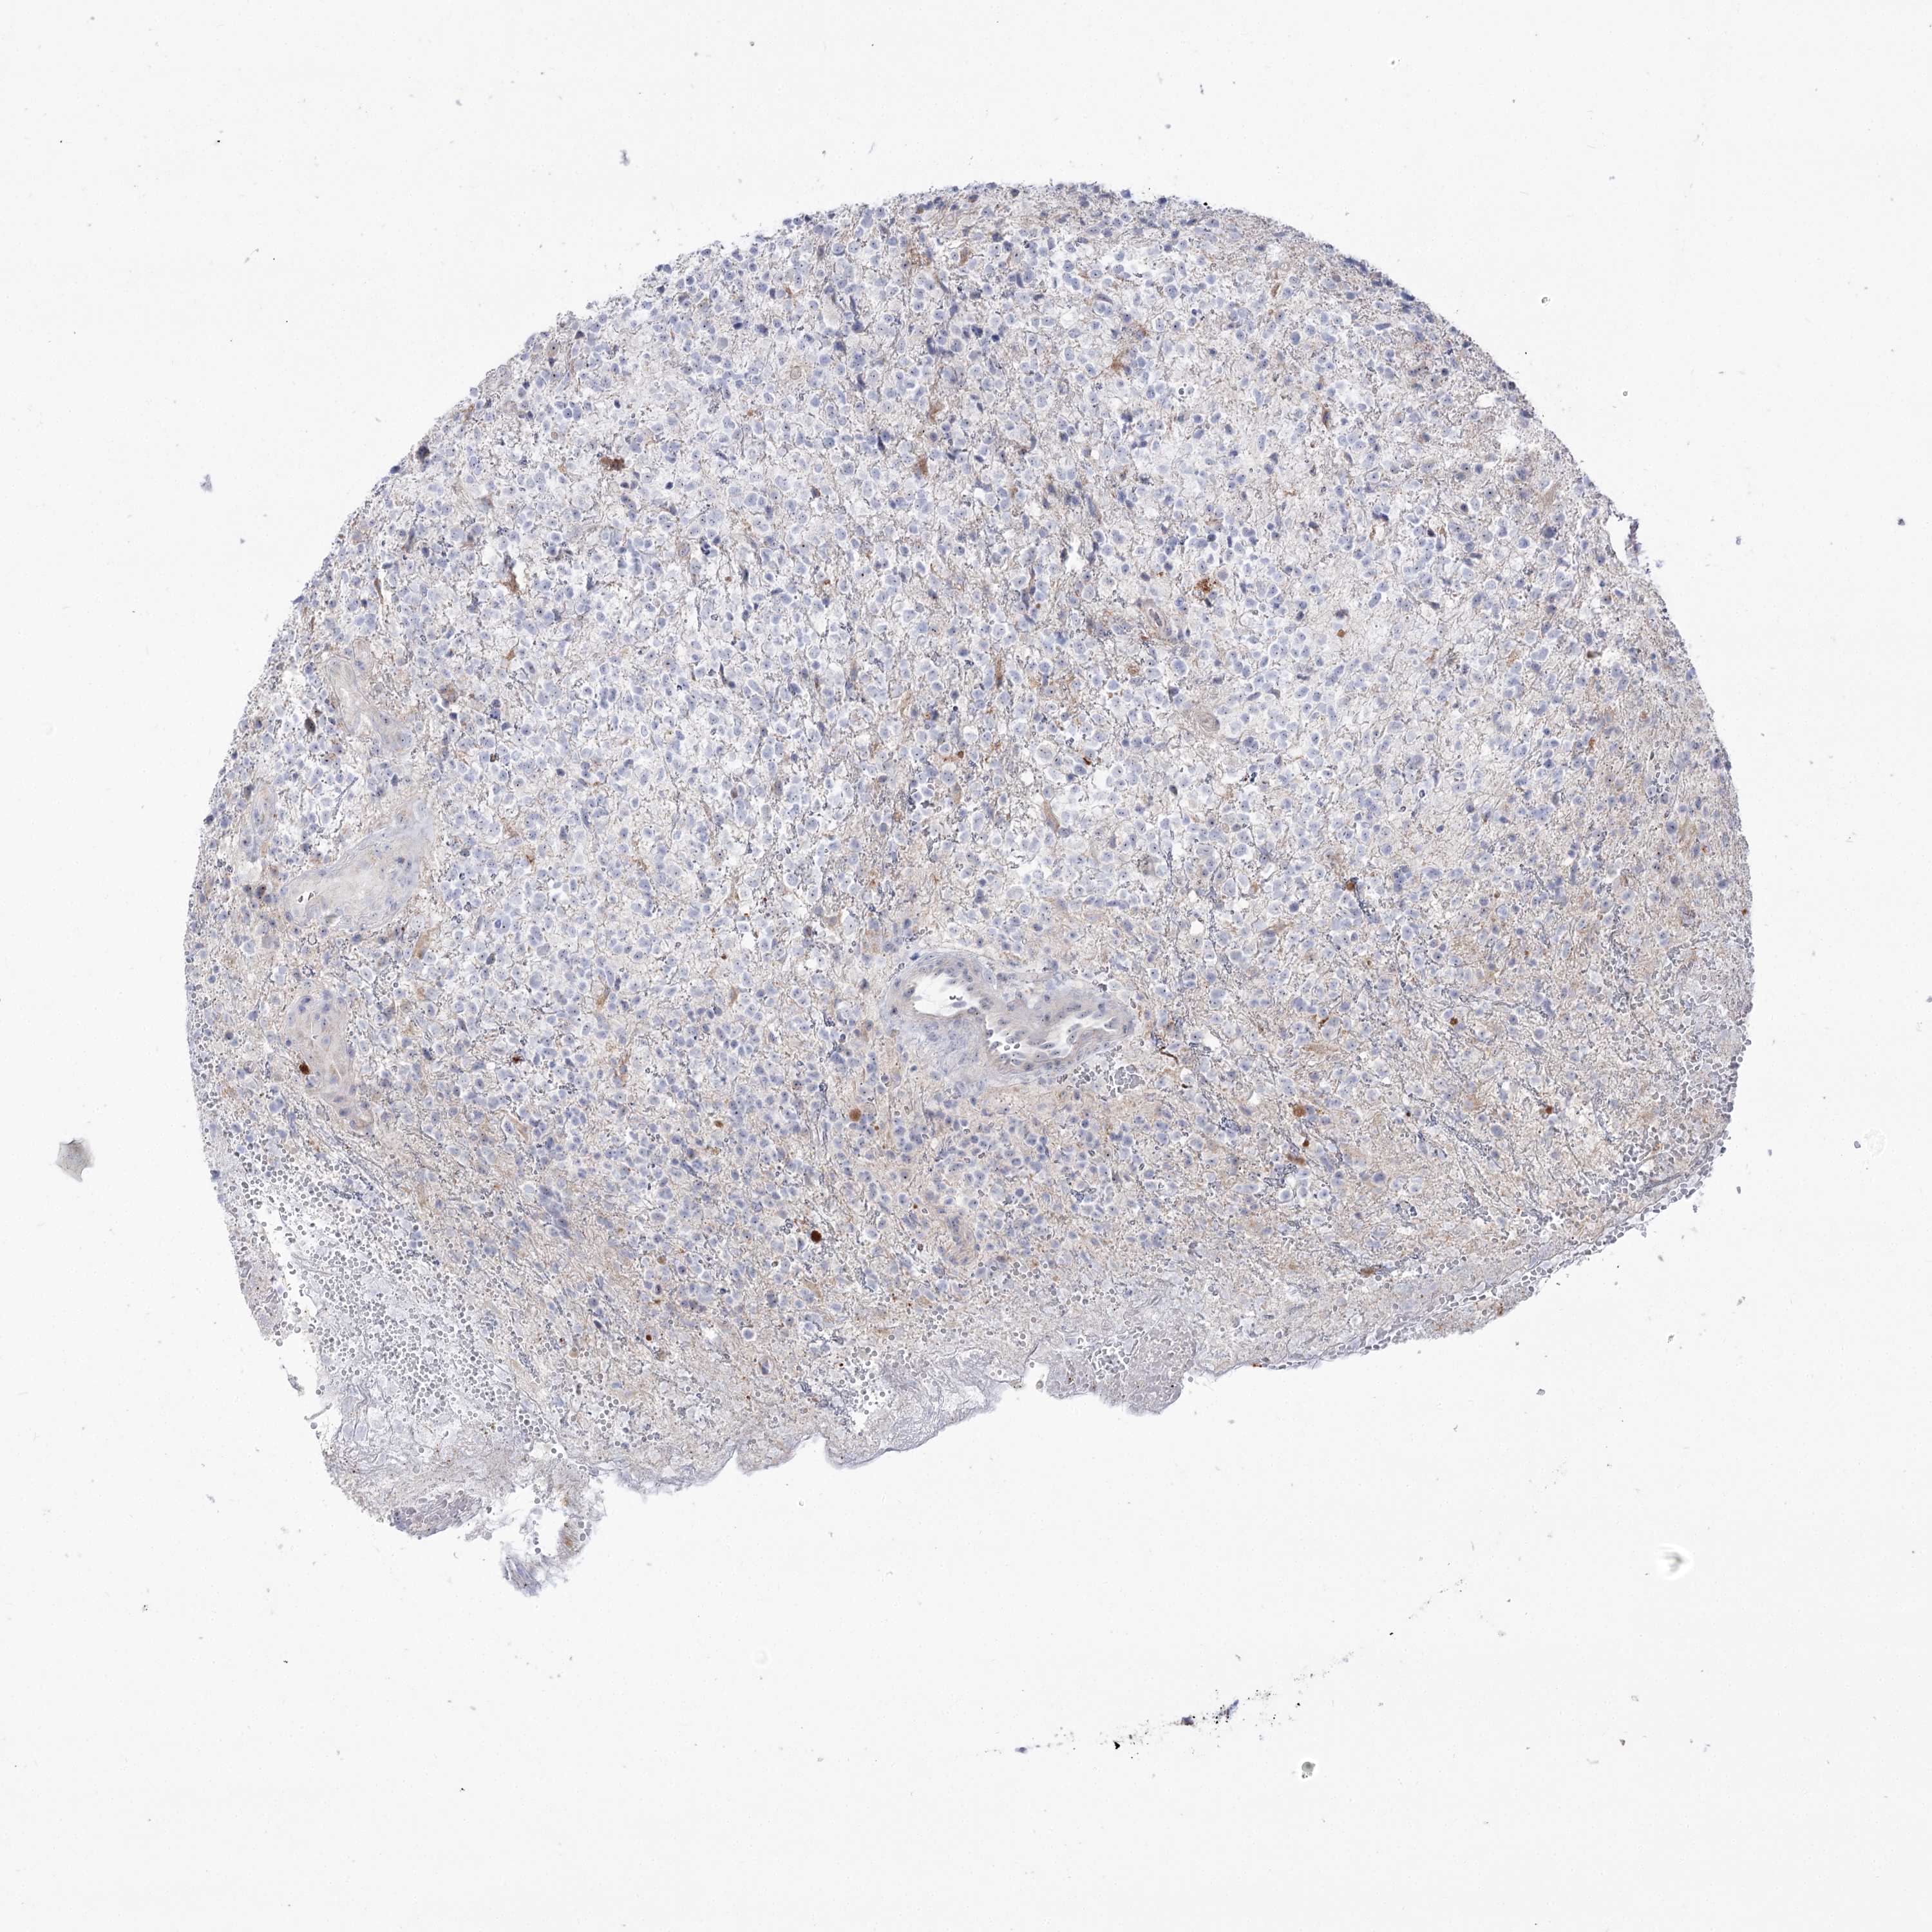

GLIOMA - Protein expressioni

A mouse-over function shows sample information and annotation data. Click on an image to view it in a full screen mode. Samples can be filtered based on level of antibody staining by selecting one or several of the following categories: high, medium, low and not detected. The assay and annotation is described here.

Note that samples used for immunohistochemistry by the Human Protein Atlas do not correspond to samples in the TCGA dataset.

Antibody stainingi

Antibody staining in the annotated cell types in the current human tissue is reported as not detected, low, medium, or high, based on conventional immunohistochemistry profiling in selected tissues. This score is based on the combination of the staining intensity and fraction of stained cells.

Each image is clickable and will lead to virtual microscopy that enables deeper exploration of all samples and also displays staining intensity scores, fraction scores and subcellular localization as well as patient and tissue information for each sample.

Antibody HPA038208

Antibody HPA038209

Staining

High

Medium

Low

Not detected

Intensity

Strong

Moderate

Weak

Negative

Quantity

>75%

75%-25%

<25%

None

Location

Nuclear

Cytoplasmic/membranous

Cytoplasmic/membranous,nuclear

Glioma, malignant, High grade

Glioma, malignant, Low grade

Glioblastoma, NOS